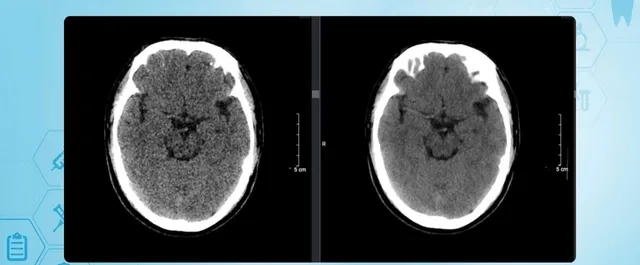

Hình ảnh chụp CT não của người bệnh chưa thấy rõ vùng tổn thương não.

Thông tin từ Bệnh viện Hữu Nghị Việt Tiệp cho biết, mới đây các bác sĩ khoa Đột quỵ vừa cứu sống một người bệnh (nam, 41 tuổi) bị đột quỵ não. Trước đó, bệnh nhân nhập viện trong tình trạng liệt hoàn toàn nửa người trái, méo miệng, nói khó. Tại Khoa Cấp cứu, người bệnh được chụp CT sọ não, kết quả chưa ghi nhận tổn thương rõ ràng. Đáng chú ý, người bệnh có tiền sử hút thuốc lào 26 năm nhưng không mắc bệnh mạn tính nào khác. Các bác sĩ chẩn đoán đây là trường hợp nhồi máu não không rõ thời điểm khởi phát. Thời điểm bình thường gần nhất được người nhà ghi nhận là khoảng 7 tiếng trước đó, tức là người bệnh đã vượt qua "thời gian vàng" chỉ định tiêu sợi huyết theo tiêu chuẩn thông thường.